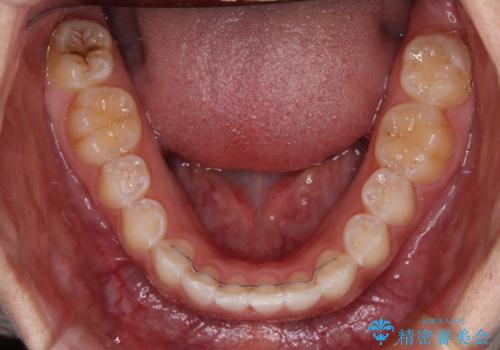

前歯のデコボコを治したい インビザライン矯正治療

上下顎ともに歯列全体の後方移動とIPR(歯と歯の間を削る)によってデコボコが解消するように設計し、インビザラインにより治療を行うこととしました。

強い咬合力による臼歯部の噛みにくさと、それに伴う歯の移動の鈍さに悩まされ、非常に長い期間を要することとなりました。

上下正中位置は、治療開始時よりは改善したものの、ここが限界であろうというところでのゴールとなりました。

下顎前歯の大半が隠れている状態ですが、左右への歯ぎしりはスムーズに行うことができ、就寝時には後戻り防止も兼ねて、食いしばり対策としてマウスピースの使用を継続するようお願いしております。